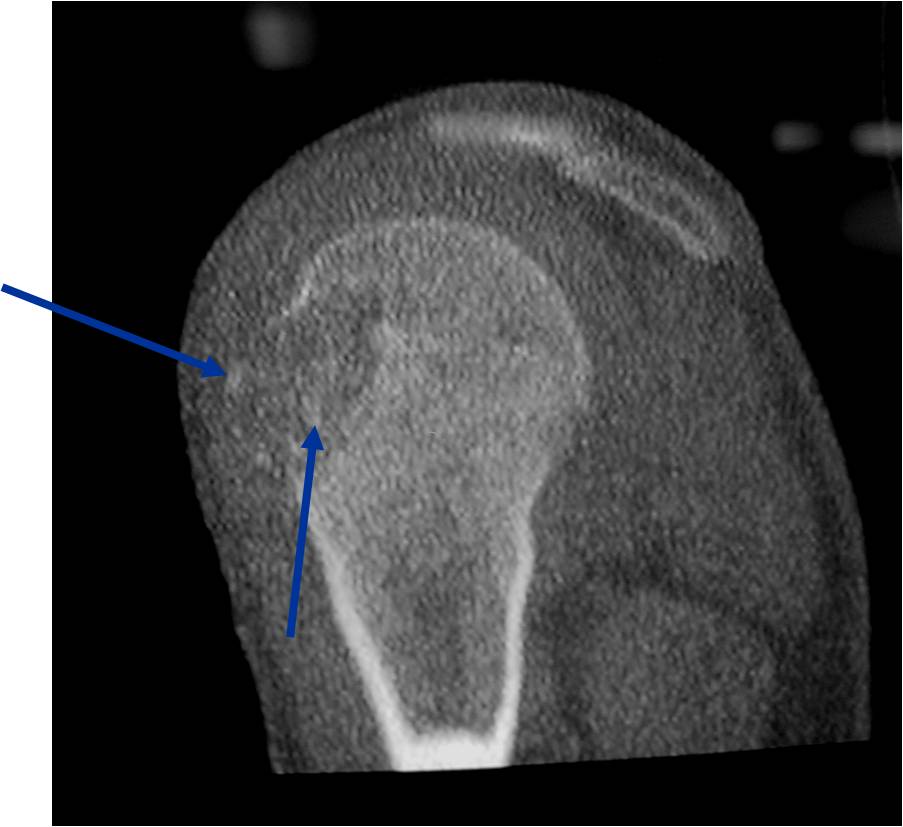

CT appearance:

- Most useful for detecting subtle mineralization not apparent on X-rays

- Useful for identifying intact periosteum around any expansile soft tissue component

- surrounding thin reactive shell of bone/mineralization (Egg Shell Rim of Calcification)

- helps place the tumor in a benign category

- helps evaluate:

- bony quality

- extent of bone and cortical destruction

- whether the subchondral plate of bone adjacent to the articular cartilage has been destroyed or is intact